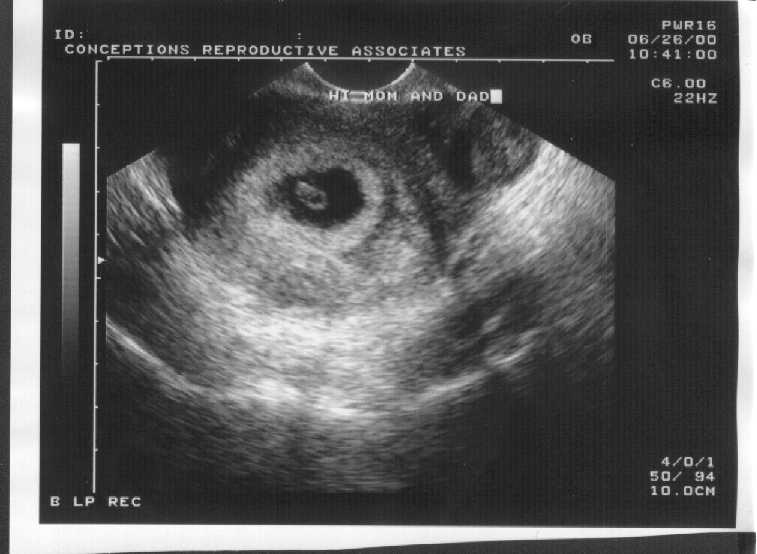

It's more of a fish than an embryo at just seven weeks. Smaller than my fingertip, it's 7.7 mm long, slender as a tadpole with a lump of a heart, just a quarter of the size larger than it's egg sack and swimming with the dark, clear depths of the embryonic sack. It's tail is stuck to the egg sack, still drawing nutrients. Turns out that it was the right ovary that made the egg that got fertilized. So it looks like the surgery was all for the good. Keenness. With the ultrasound they could tell that the heart was beating at 160 beats per minutes, which seems ultrafast, but the thing is so tiny. We could see the few pixels flipping back and forth, for the motion of its heart, which seems as healthy as they can tell, for now.

So far, everything looks good. Which is pretty good, because this is the time period from which about 95% of the embryos will actually not have an early miscarriage, or so the doctors say. And, at this point, if it does miscarry it's because of severe genetic faults, not anything I could do. So that's reassuring. I seem to have, half unknowingly, gotten through the most uncertain bits. The doctor handed us our 'first baby pictures', a smear of grey against a black egg shape amid other uncertain greyness. It seems a good enough metaphor.